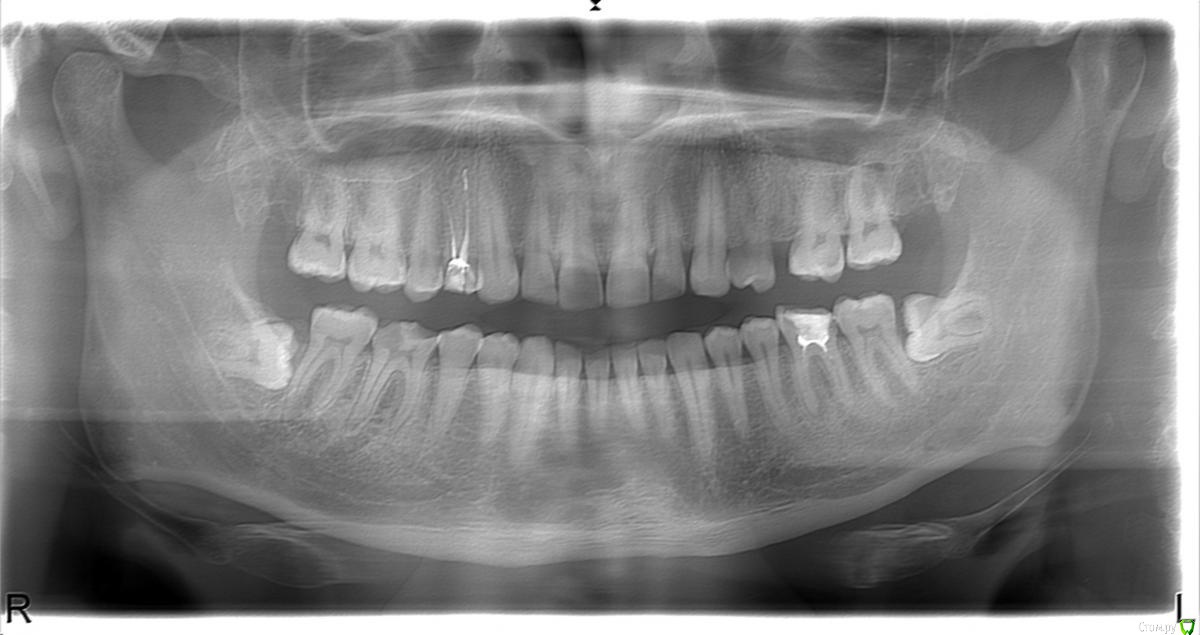

максим83 Опубликовано 4 февраля, 2018 Поделиться Опубликовано 4 февраля, 2018 (изменено) советуют удалить. Какова сложность, местные хирурги не берутся - так ли это (фото прилагаю)... Изменено 4 февраля, 2018 пользователем максим83 Ссылка на комментарий

Борис80 Опубликовано 5 февраля, 2018 Поделиться Опубликовано 5 февраля, 2018 8е удалять, сложность , если можно применить такое слово, не запредельная. Вполне рабочая ситуация Ссылка на комментарий

Irouil Опубликовано 5 февраля, 2018 Поделиться Опубликовано 5 февраля, 2018 Правый зуб я бы не удалял, левый безусловно убирать. Удаление сложное, но все относительно. Сложнее всего обеспечить спокойное заживление после удаления. 2 Ссылка на комментарий

Bier Опубликовано 7 февраля, 2018 Поделиться Опубликовано 7 февраля, 2018 я за удаление обоих зубов, сложность между легкой и средней. Ссылка на комментарий